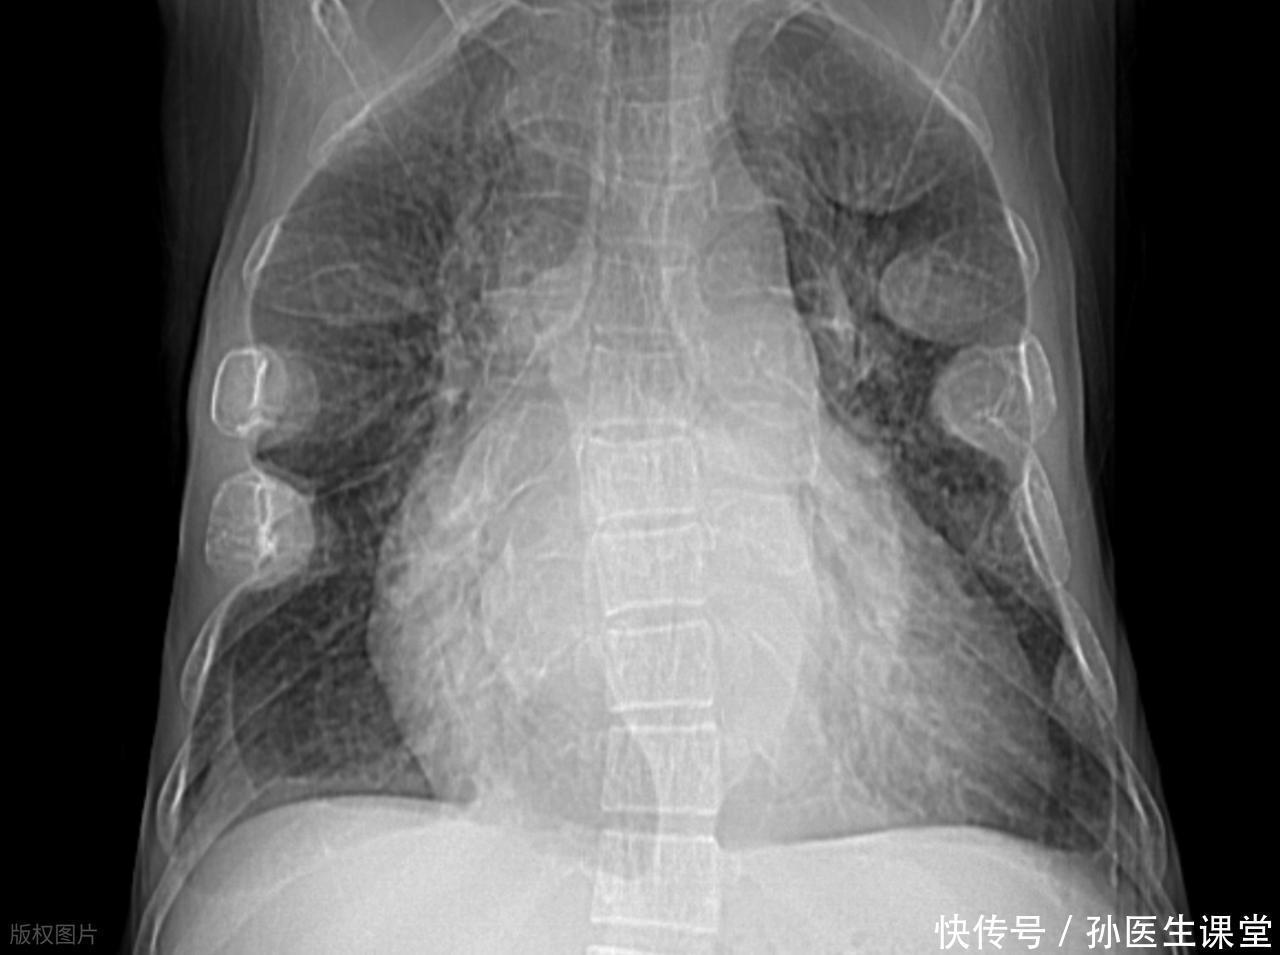

另外,腹部肿块也不容忽视。腹部的一些恶性肿瘤,如肝癌、胃癌、卵巢癌等,都可能在腹部形成肿块。曾经有一位50岁的王先生,因为腹部摸到肿块且伴有腹胀、食欲减退等症状去医院检查,最终被确诊为肝癌晚期,错过了最佳治疗时机。